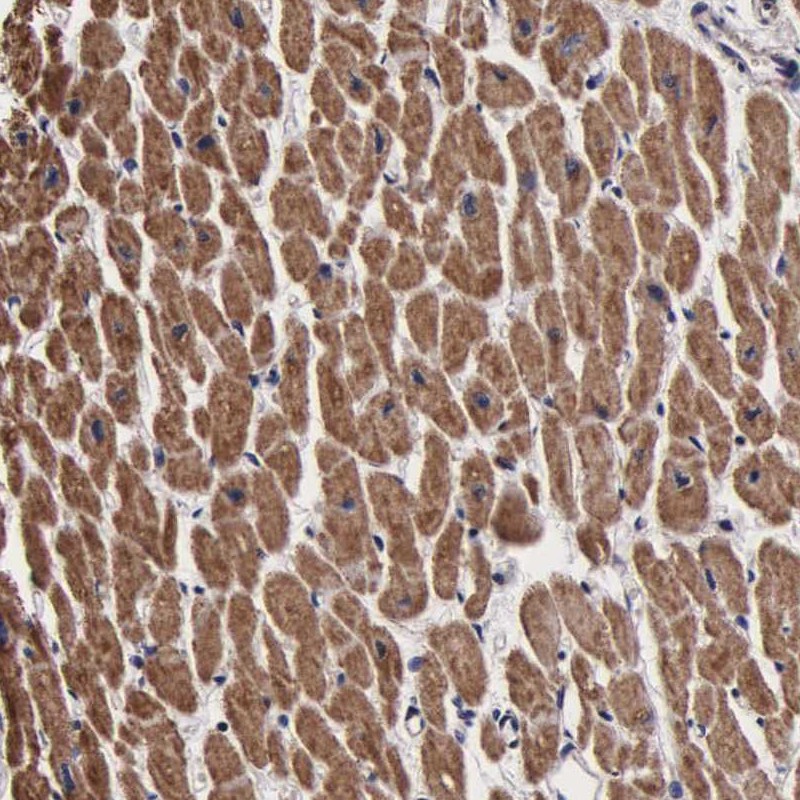

Immunohistochemical staining of human heart muscle shows moderate cytoplasmic positivity in myocytes.